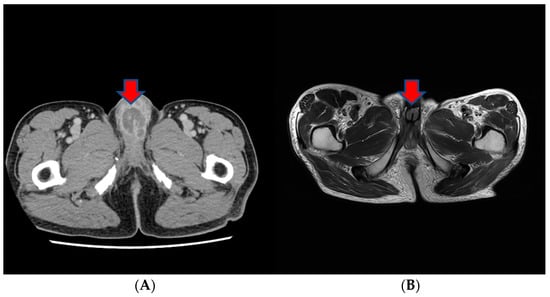

Approximately three months prior to presentation, he sought medical attention for right flank pain and underwent a computed tomography (CT) scan. Before the visit, the patient did not have any significant physiological or medical history. The findings revealed an approximately 13 cm sized heterogeneous mass in the lower pole of the right kidney, exhibiting robust arterial enhancement. It displayed invasion into the adjacent psoas muscle, indicating a potential RCC diagnosis. Additionally, evidence of tumor thrombosis in the inferior vena cava (IVC) was also observed (Figure 1). During the same CT examination, a specific finding of right scrotal varicocele was noted. This was likely attributed to thrombosis and extrinsic compression of the right gonadal vein due to the large mass in the right kidney. CT imaging of the chest showed no evidence of pulmonary mass or adenopathy.

Figure 1.

The CT scan of the abdomen of our patient. (A) An approximately 13 cm sized heterogeneous mass in the lower pole of the right kidney, exhibiting robust arterial enhancement. (B) The finding of tumor thrombosis in the inferior vena cava (IVC).